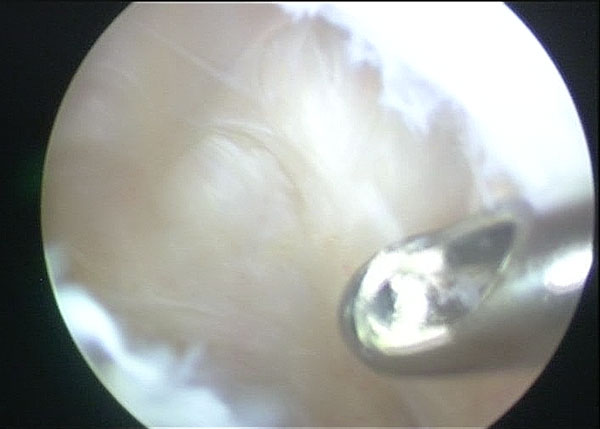

Arthroscopic Management of Baker's CYST